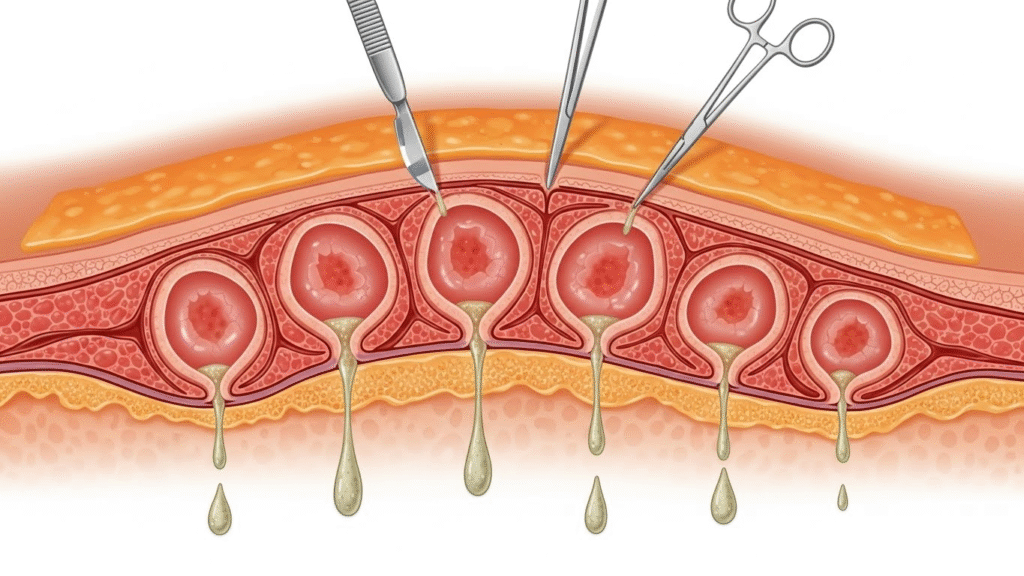

🩺 How Doctors Treat Multi-Cyst Cases Safely

1️⃣ Deep Incision & Drainage

Opening the entire area to reach every sac.

2️⃣ Removal of Each Cyst Lining

If the lining stays, the cyst grows back.

3️⃣ Cleaning the Pocket

Flushing out oil, debris, and infected fluid.

4️⃣ Stitches to Prevent New Pockets

Closing the skin properly reduces future buildup.